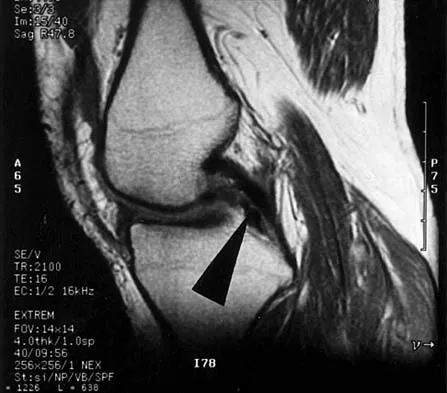

A 28-year-old man has left knee pain after a snow skiing accident. The MRI scan shown in Figure 47 reveals which of the following?

Explanation